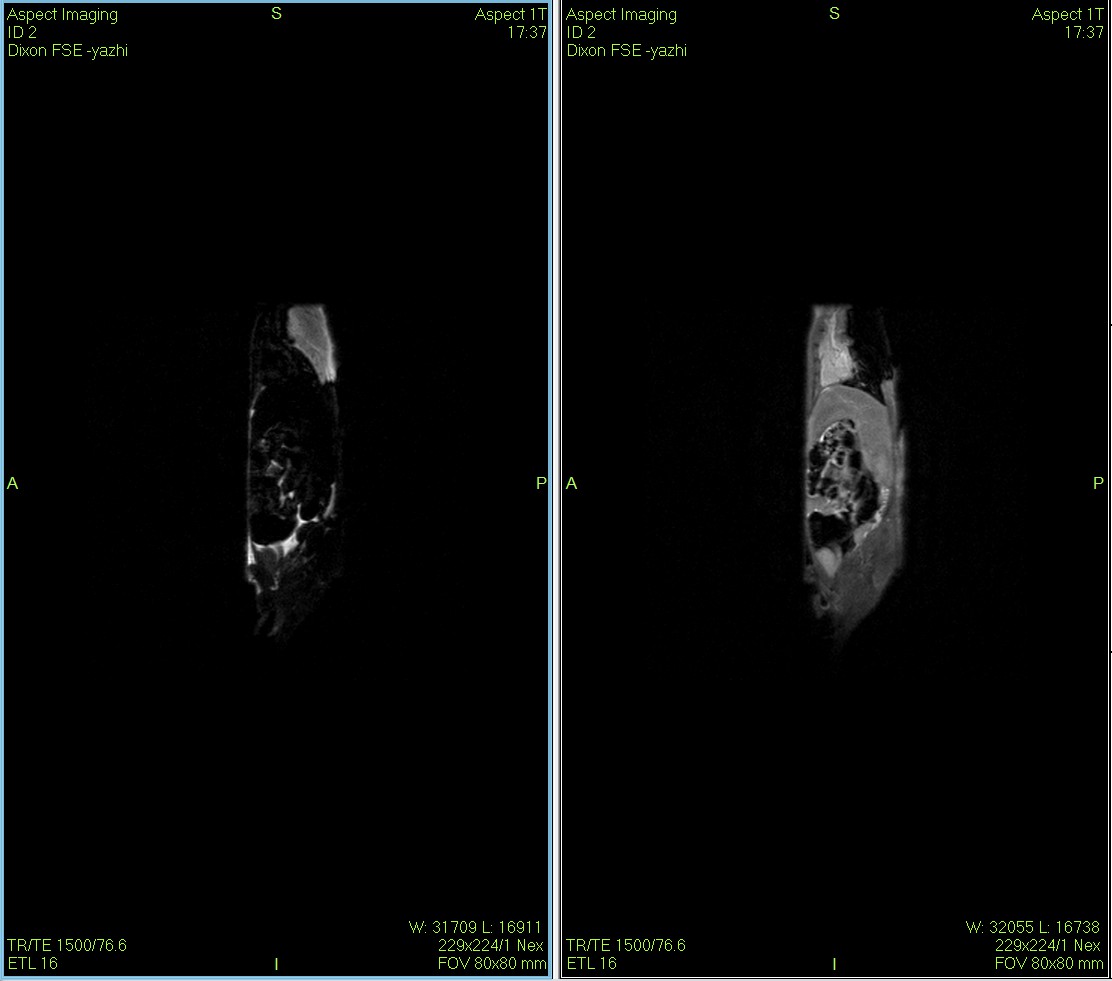

Dixon序列用于大鼠、小鼠水脂分离磁共振成像-脂肪抑制技术

Dixon脂肪抑制技术是由Dixon 提出,其基本原理是利用水、脂肪的化学位移差异,使用不同的回波时问,分别采集水和脂肪质子的in Phase 和 opposed -phase两种回波信号。

使用仪器: 小动物核磁共振成像仪NM21-040H-I 小动物核磁共振成像仪NM20-060H-I 小动物核磁共振成像仪NM42-040H-I